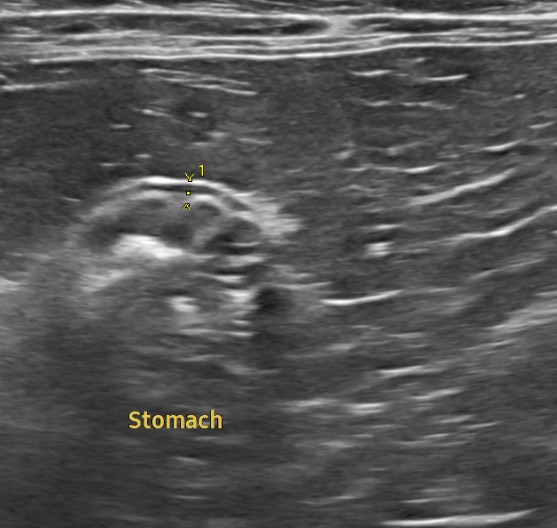

이번 아이처럼 특별한 증상을 보이지 않는 경우라도, 혈액검사·초음파·흉부 및 복부 영상검사 등을 한 번에 묶어 진행하면 현재 장기 기능을 객관적으로 확인하고, 잠재적인 질환의 방향성까지 파악할 수 있습니다.

혈액검사에서는 주요 장기 수치, 염증 수치, 전해질 균형 등을 확인했고, X-ray는 흉부·복부 전반의 장기 구조를 점검했습니다. 초음파는 장기 실질 구조나 미세한 이상까지 확인할 수 있어 검진의 핵심 항목으로 포함됩니다. 치과검사는 일반적으로 마취가 동반되어, 구강전용 엑스레이 촬영을 해야 정확한 판단이 가능하지만 치과전문 병원인 만큼 육안으로 기본적인 검사는 해드리고 있습니다.